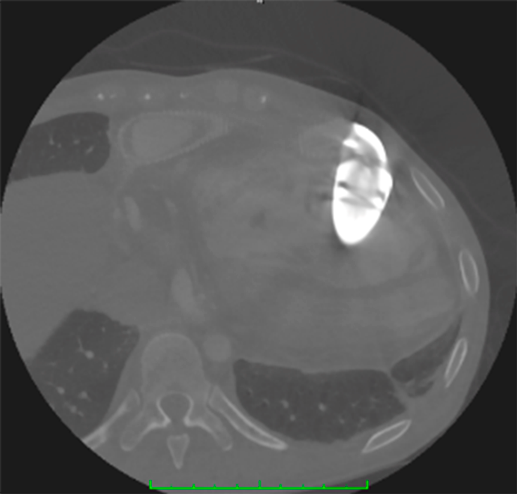

体心室右室に対するVAD

心房スイッチ術後の完全大血管転位,生理学的修復術後の修正大血管転位などでは体心室が右室となる.通常の左室心尖部と異なり,右室は前面にあるため,脱血管の挿入には注意が必要である.我々の経験では心房スイッチ術後の完全大血管転位の患者にJarvik2000を装着した症例で,脱血管が心室中隔に向かってしまった例がある(Fig. 6).本症例では,最終的にEVAHEART2のtipless cannulaを用いてコンバートを行い17),移植へ到達した.また,右室は左室に比べて疎な肉柱が発達しているため,脱血管の閉塞を防ぐために十分に肉柱の切除を行うことが重要となる.修正大血管転位の患者に対してVADを装着したものとしては,HVADを装着した症例18, 19),Jarvik2000を装着した症例20)などが報告されている.

Pediatric Cardiology and Cardiac Surgery 39(3): 161-168 (2023)

Fig. 6 心房スイッチ手術後の完全大血管転位の患者の右室に対してJarvik2000が挿入されているが,中隔方向へ向かっており,脱血不良を来している.